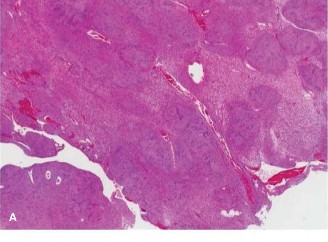

A 46-year-old male presents to you for a second opinion. He recently underwent surgery to remove a mass from …